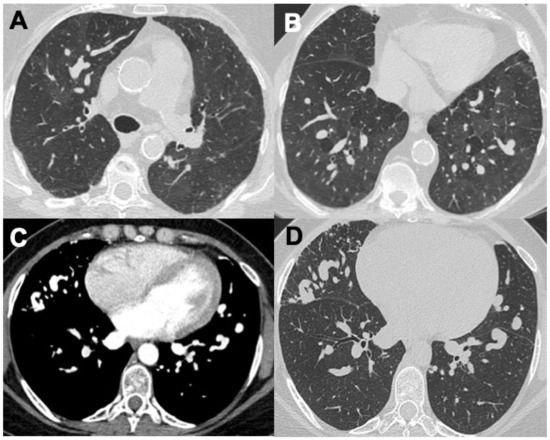

Behçet Disease (BD) and Hughes–Stovin Syndrome (HSS)

| Behçet disease (BD) |